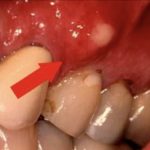

Если говорить о том, что представляет собой чирий на десне, то это просто гнойник, который возникает из-за того, что в пораженную область проникла инфекция. Прежде всего, это происходит, если пациент не уделяет должного внимание гигиене. Из-за того, что в ротовой полости постоянно присутствует патогенная микрофлора, она в любой момент может проникнуть даже в небольшую ранку. Если при этом у пациента еще и ослаблен иммунитет, заболевание развивается еще быстрее. Инфекция чаще всего попадает в организм следующим образом:

Прорезывание зубов мудрости часто вызывает травмы десен. Это происходит, если резец встречает на своем пути преграду в виде «кармана» из мягких тканей. Пытаясь прорвать его, восьмерка травмирует слизистые оболочки. Поскольку это процесс длительный, то пару дней рана остается открытой (пациент чувствует это, поскольку область постоянно болит). Именно через нее внутрь попадают бактерии. Очень важно анализировать симптомы, сопутствующие данным процессам, чтобы вовремя обратиться к врачу, купировав опасное воспаление.